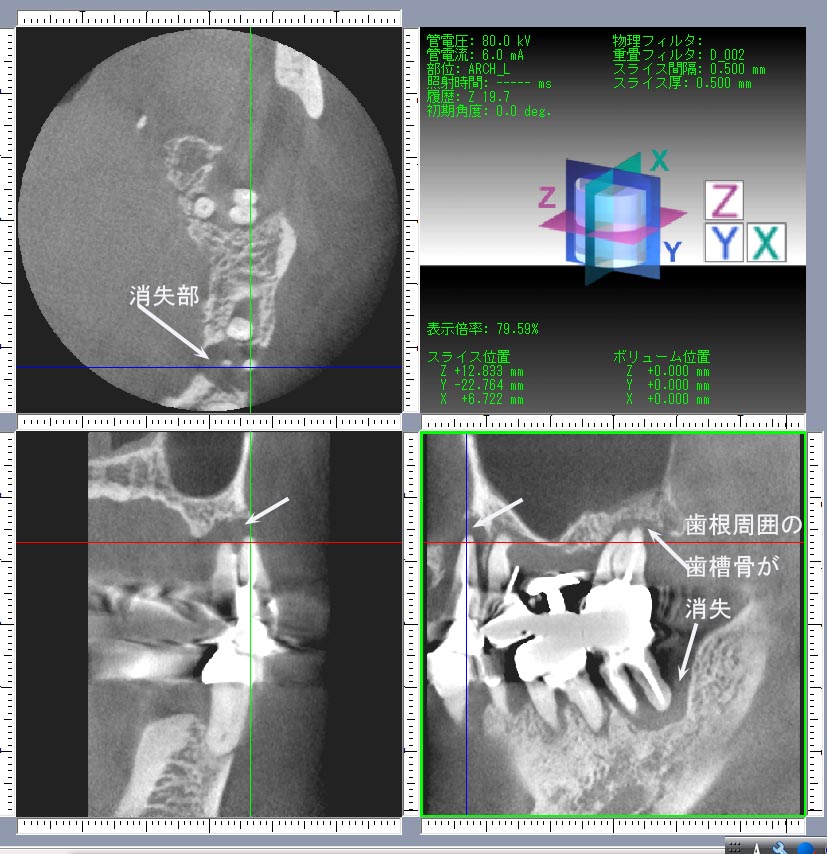

Photo-8.歯槽骨が破壊されたCT画像

thumb-1

また、歯を取り巻いている骨の量や密度も個人によって大きく異なっている以上、FDCでは平面レントゲンだけでなくCT撮影によって早期から歯周病罹患後の進行リスクを予測しています。歯根周囲の歯槽骨の状態を考えずに定型処置をおこなっても同じ治療結果にはなりません。さらに、歯槽骨の病的変化は従来の免疫学だけでは解決できない問題がありますのでFDCは新しい考え方として「骨免疫学」の視点からの研究をすすめています。

3-2.歯の動揺は赤信号

歯周病診断は歯肉の状態よりも、歯肉から見えない歯根をとりまいている歯槽骨の病的変化を早期の段階で正確に診断することが最も重要です(CT撮影が必要)。日常での注意点は歯の動揺です。たえず血や膿が出るだけでなく、歯肉がしばしば腫れてくるようになるとすでに重症になっています。このシグナルを無視していると加齢の影響が加わり、いつのまにか病状が急速に進行し多数の歯を喪失いたします。